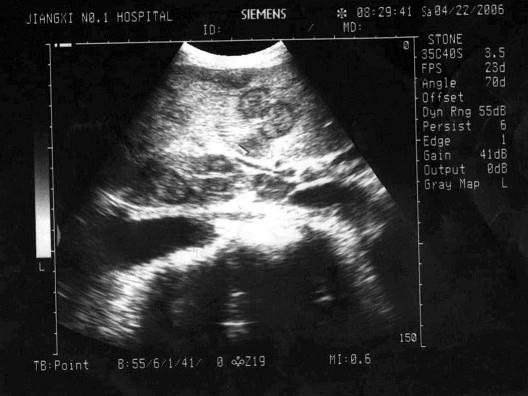

图中显示图像为?(?)A.牛眼征B.靶环征C.套筒征D.蟹钳征E.以上都不是

选项 A.牛眼征 B.靶环征 C.套筒征 D.蟹钳征 E.以上都不是

答案 A